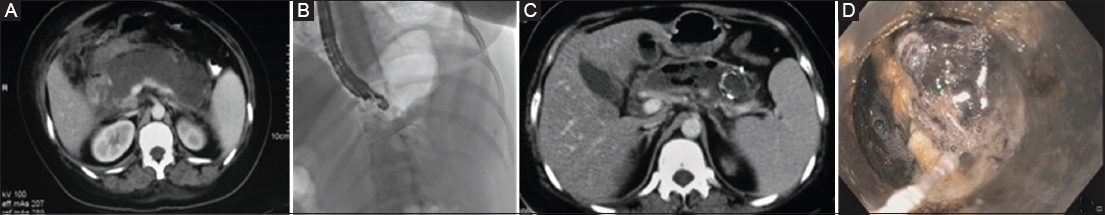

The procedure was technically successful in all patients in both groups (Fig. 2,3), whereas clinical success was significantly higher in the LAMS group: 40 (89%) patients vs. 10 (48%) patients; P<0.001. All patients in the LAMS group underwent stent removal within 6 weeks of placement, as per protocol. In the LAMS group, 5 patients required rescue surgery because of bleeding accompanied by ongoing sepsis (during necrosectomy in 3 patients and post necrosectomy in 2 patients) and persistent necrotic collection, whereas 11 (52%) patients in the MPS group required rescue surgery (bleeding resulting in hemodynamic compromise in 5 patients, during necrosectomy in 4 patients and post necrosectomy in 1 patient, and ongoing sepsis with persistent necrotic collection in 6 patients). ETN was performed more frequently in the MPS group than in the LAMS group: 18 (86%) patients vs. 26 (58%) patients, respectively; P=0.02. Patients with MPS required more necrosectomy sessions to achieve a successful outcome compared to those with LAMS (6.1±1.9 vs. 4.1±1.1; P=0.009). Additional percutaneous drainage was needed more frequently in the MPS group than in the LAMS group: 10 (47.1%) vs. 6 (13%), respectively; P=0.004. Patients in the LAMS group required fewer days for resolution compared to the MPS group: mean of 22 days vs. 34 days; P<0.001. Four (19%) patients in the MPS group succumbed to their illness as compared to 3 (6%) patients in the LAMS group (P=0.19).

thumblarge

Figure 3 (A) Computed tomography at day 19: an ill-defined pancreatic necrosis. (B) LAMS being deployed. (C) Computed tomography after metal stent placement. (D) Cap-assisted endoscopic necrosectomy LAMS, lumen-apposing metal stents